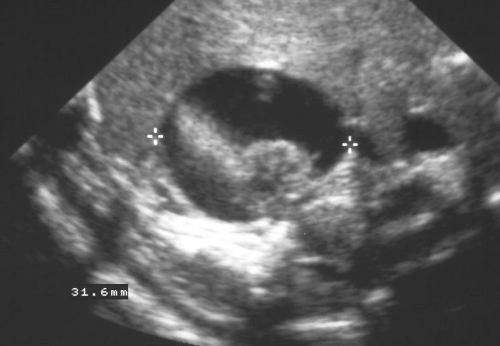

Ultrasound is quick, and a relatively inexpensive technology, but it has significant limitations in adrenal scanning. The adrenal glands are difficult to examine by ultrasound because of their small size, their location high in the abdomen under the rib cage, and the presence of retroperitoneal fat and bowel gas. In thin patients, the normal adrenal may be identified.An anterior or lateral approach may be necessary, particularly for the right adrenal gland, which occasionally can be seen through the liver. Bowel gas often impairs visualization of the left adrenal gland. A variety of patient positions and scanning windows are often required to adequately examine the glands.Since CT and MRI have so many diagnostic advantages, ultrasound is not used as the primary modality for the adrenal glands. Ultrasound can help in the characterization of large adrenal masses, as well as to define whether a suprarenal mass originates from the kidney or the adrenal. |

This is a case of neonatal hemorrhage, showing a complex mass with both solid and cystic components. Courtesy of: Ashley Davidoff, M.D. |

This image represents a solid mass that is half the size of the kidney below the mass. A mass of this size typically indicates a primary carcinoma, however, this case represents a large pheochromocytoma. Courtesy of: Ashley Davidoff, M.D. |